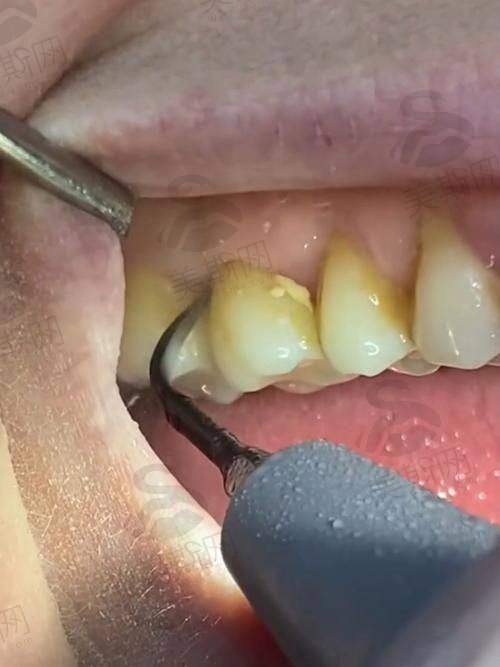

牙科洗牙价格表

成人超声波洗牙 + 抛光单人套餐 | 20.9元起 |

含喷砂洁牙洗牙 | 104元起 |

成人超声波洗牙 + 抛光单人套餐(工作节假日通用) | 27.9元起 |

去除烟渍/茶渍 | 139元起 |

2人超声波舒适洗牙 | 41.9元起 |